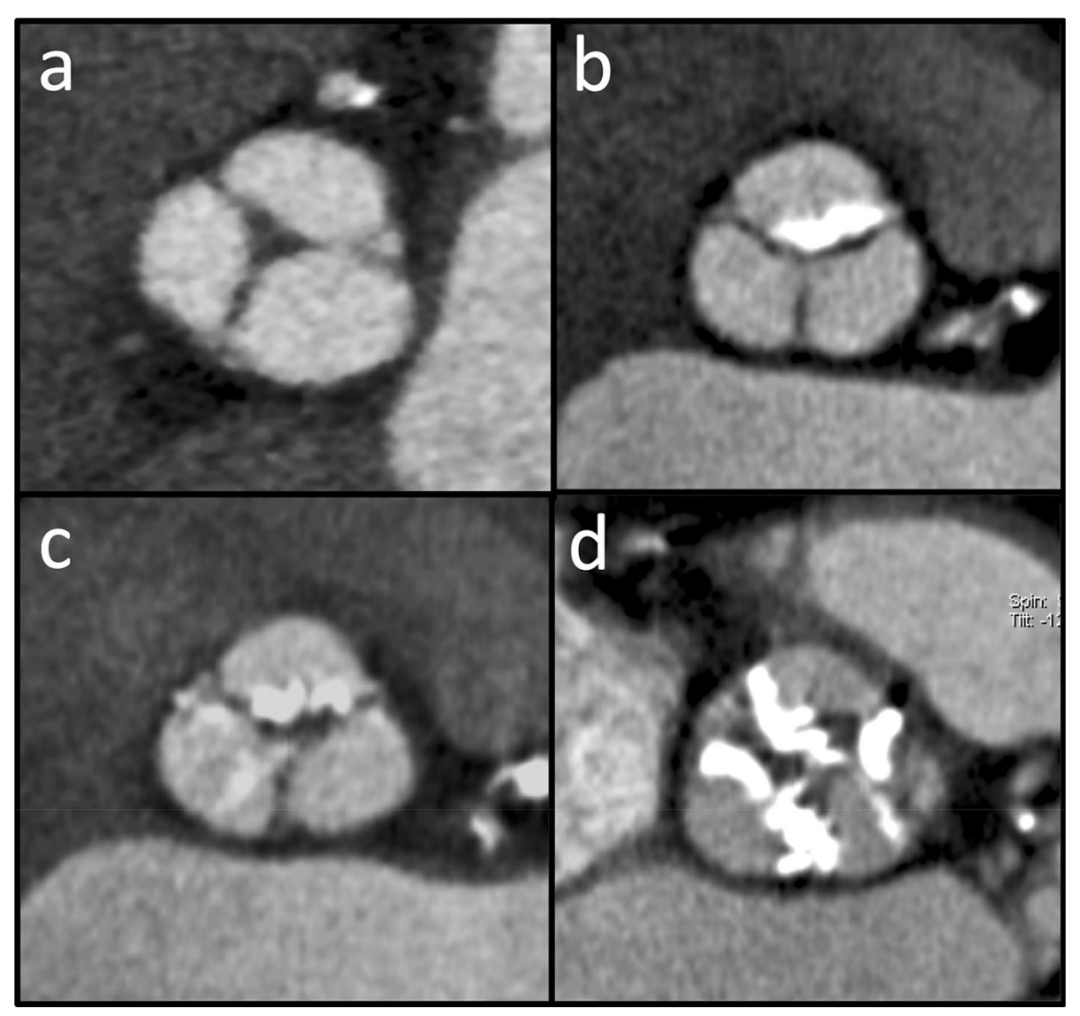

主动脉瓣作为主动脉根部的一部分,结构复杂,,由纤维骨架支撑,从心室-动脉交界处延伸至窦管交界处。主动脉瓣通常由三个瓣叶组成,瓣叶以各自的 Valsalva 窦(右、左和无冠状)命名,并通过向外的半圆形边缘锚定在主动脉壁上。瓣叶附着缘和瓣环之间的连接点称为接合部(Commissures)。主动脉根部形态的评估应包括主动脉瓣形态的描述(瓣叶数量、厚度、钙化和对合),以及不同水平面(主动脉瓣环、Valsalva窦和窦管交界处)主动脉管腔尺寸的测量(图1)。由于主动脉根部的解剖构造存在个体差异,并且其方向不符合标准解剖平面,因此必须使用特定的倾斜二维 (2D)平面进行评估(图2)。商用图像分析软件中提供的 2D/3D 重建工具能获取特定的主动脉平面(长轴和正交平面)。这些主动脉平面可以由具有特定 TAVI 模块的专用软件自动生成,能够提取主动脉中心线并创建与主动脉根部完全正交的图像(横截面成像),或者在双斜可视化引导下使用横截面法手动重建。在瓣膜严重退行性变的患者中,例如在主动脉瓣严重钙化的TAVI 候选患者中,,通过超声心动图评估瓣叶数量可能很困难;多期或至少双期(收缩期和舒张期)重建的 ECG 门控 CT 血管造影可能有助于确定瓣膜的形态,特别是区分先天性解剖变异,例如二叶式主动脉瓣 (bicuspid aortic valve, BAV)。与三叶式主动脉瓣相比,BAV的退行性变发展更快,出现狭窄的时间更早且发生率更高,并且存在于越来越多的 TAVI 候选患者中。虽然 BAV 不是 TAVI 手术的禁忌症,但它常因大块的瓣膜钙化、较大的瓣环尺寸、增加的瓣环椭圆度、不对称的瓣叶和升主动脉扩张,可能会增加手术的复杂性。因此,BAV 患者发生手术并发症的风险增加,如装置贴壁不良、高残余压差或显著残余主动脉瓣关闭不全(AR)、瓣环破裂或主动脉夹层以及更高的 TAVI 术后永久性起搏器植入的发生率 。

主动脉根部尺寸评估

主动脉根部连接心脏和体循环,是一个复杂而精密的结构,由瓣环、主动脉瓣、Valsalva 窦和窦管交界处组成。在 CT 图像上,主动脉瓣环是对应于主动脉瓣基底部的解剖部位,三个瓣叶的最低插入点(铰链点)形成的环平面,位于心室-动脉交界处的正下方。准确测量主动脉瓣环和主动脉根部是评估TAVI可行性、正确的术前计划和装置选择(瓣膜尺寸和设计)的基础。沿常规解剖平面(冠状面和矢状面)重建或单斜重建粗略测量瓣环尺寸是不可行的。为得到可靠的测量结果,必须提供最佳质量的图像以及对重建斜面的正确定位,这是装置选择的基础。图2显示了如何从传统平面开始采用双斜入路获得主动脉瓣环的正确横截面图像。瓣环尺寸测量需要标准化和可重复的方法。瓣环尺寸的测量应包括长轴和短轴直径、截面积和周长(图3),所有测量值都可通过(半)自动衰减/基于Hounsfield 单元的轮廓检测得到。面积和周长得出的有效直径是在植入装置后瓣环为正圆形的几何假设下计算的。然而,这些方法存在固有误差,并且当瓣环形状特别偏心时,可能导致所选假体尺寸过小或过大,从而导致瓣周漏或植入的瓣膜展开不完全的风险。瓣环在心动周期中也会发生构象和尺寸变化:其形状在收缩期更偏圆形,在舒张期主要呈卵圆到椭圆形。由于与左心室射血相关的径向力的增加,与舒张期相比,收缩期瓣环的短轴直径、截面积和周长更大。因此,如果可获得多相数据,应首选在收缩期重建的图像来测量瓣环尺寸,因为在不同时相变化很大的患者中,使用舒张期测量可能会导致 TAVI 假体尺寸过小,导致瓣周漏的风险增加(图 4)。然而,在心率较快或心律失常的患者中,收缩期图像更容易受到心脏跳动伪影的影响,如果在扫描采集期间进行剂量调制,则通常会表现为图像噪声增加。在这些情况下,舒张期图像会提供更好的图像质量。主动脉瓣狭窄通常以瓣叶上不同程度的钙沉积为特征,钙沉积量随狭窄程度而增加,提示预后较差。特别是钙化性主动脉瓣狭窄的患病率随着年龄的增长而增加,在年龄 > 65岁的患者中达到峰值,这是最常接受TAVI的人群。主动脉瓣钙化程度可以通过 CTA 图像进行主观定性评估(无、轻度、中度和重度,图5),但是基于ECG门控的非增强CT 图像的Agatston 评分系统已被提议用于定量评估和术前风险分层,最常用的鉴定严重主动脉狭窄的阈值是男性 2000 、女性 1200。瓣膜钙沉积的分布应根据分布模式(对称/不对称、弥漫/局灶)、相对于瓣叶(瓣叶边缘、连合处和附着点)和 LVOT 的位置进行常规描述。当输送系统打开时,钙化的天然瓣叶被挤压到主动脉壁上。许多研究表明,无论是使用自膨瓣或球扩瓣,装置落脚区(landing zone)的钙化程度及分布模式对TAVI 后的手术结果有显着影响。主动脉瓣的大块或偏心钙化可能会妨碍假体的完全打开或正确锚定。事实上,附着在瓣叶边缘或连合处的钙化结节会造成机械障碍,从而导致人工瓣膜与主动脉根部之间存在残余间隙,这可能会影响植入的人工瓣膜的稳定性、对锚定部位的粘附性并使装置部分变形。严重的瓣膜钙化,特别容易增加术后反流或瓣周漏的风险,导致患者难以耐受的压力超负荷。主动脉瓣的严重钙化也已知与其他并发症有关,例如球囊扩张时引起瓣环破裂,因为主动脉环钙化使瓣环刚性增加、形变能力降低、传导障碍或钙化栓塞。与严重瓣膜钙化相关的另一个潜在风险是冗长而钙化的主动脉瓣易引起的冠状动脉开口阻塞。在 TAVI 中,自身瓣叶(包括任何粘附的钙化灶或赘生物)不会像外科瓣膜置换术那样被移除,而是在假体瓣膜释放过程中移位并被压在天然主动脉壁上。自身瓣叶重叠而阻塞冠状动脉开口是 TAVI 手术的一种罕见却危及生命的并发症,发生在 0.35-0.8%之间,最常见于接受球扩瓣的患者,并且通常影响左冠状动脉。此种情况下通常需要经皮冠状动脉介入治疗。尽管文献报道的冠脉介入可行性和成功率很高,但短期和长期死亡率仍然很高。较低的冠状动脉开口、浅Valsalva窦、严重钙化和较长的原生主动脉瓣叶是易引起冠脉开口阻塞的解剖情况,因此详细的术前解剖评估对于最大限度地降低这种并发症的风险至关重要。所以需要在CT 图像上测量从主动脉瓣环平面到每个冠状动脉开口下缘的纵向距离,具体方法为收缩期在斜冠状位上应用合适定向的多平面重建(图 6)。通常认为冠状动脉口和瓣环之间的距离大于10-14毫米时发生冠状动脉阻塞的风险较低,但是更短的距离也并未被严格认定为 TAVI 的排除标准,这些测量值应与主动脉瓣长度结合考虑。就算冠状动脉口和瓣膜平面之间有足够距离,若存在瓣膜尖的重度和弥漫性钙化也要特别注意。评估还应包括在双斜投影上测量 Valsalva 窦水平的主动脉根部的横向直径和高度,因为要正确摆放特定的 TAVI 装置需要测量最小窦宽度和高度值,这因型号而异。应探查 LVOT 以验证落脚区可行并排除瓣膜下阻塞,特别是在经心尖入路的情况下,并验证是否存在钙化;在这种情况下,最好使用自膨瓣。进一步的常规测量应包括评估窦管交界处和升主动脉最大和最小直径(通常为主动脉环上方 50 毫米)。